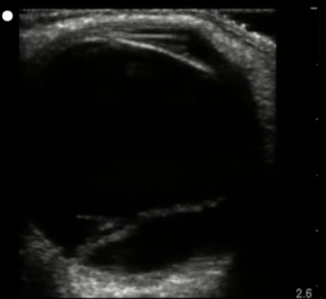

Name the pathology seen in this

transverse view of the adnexa

What is Polycystic Ovary Syndrom (PCOS)